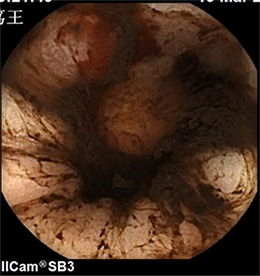

下图可见胃腔内新鲜出血与

陈旧性出血混合